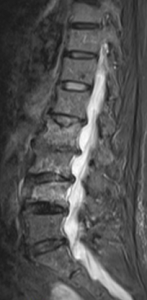

Spondylolisthese - Wirbelgleiten

Von einem Wirbelgleiten spricht man bei Verschiebung bzw. Verkippung zweier benachbarter Wirbelkörper gegeneinander. Eine Retrolisthese bezeichnet das Verschieben des kopfnäheren Wirbelkörpers gegenüber dem darunterliegenden Wirbelkörper nach hinten, analog wird das Gleiten des Wirbelkörpers nach vorn als Anterolisthese bezeichnet. Zu unterscheiden ist zwischen einem frühkindlich erworbenen Wirbelgleiten mit vorliegender Defektsituation im Zwischenwirbelbereich des Wirbelbogens (sog. Spondylolyse) und einem verschleißbedingten, degenerativen Wirbelgleiten mit intakten knöchernen Strukturen und begleitender Arthrose der kleinen Wirbelgelenke sowie Insuffizienz der Bandstrukturen.